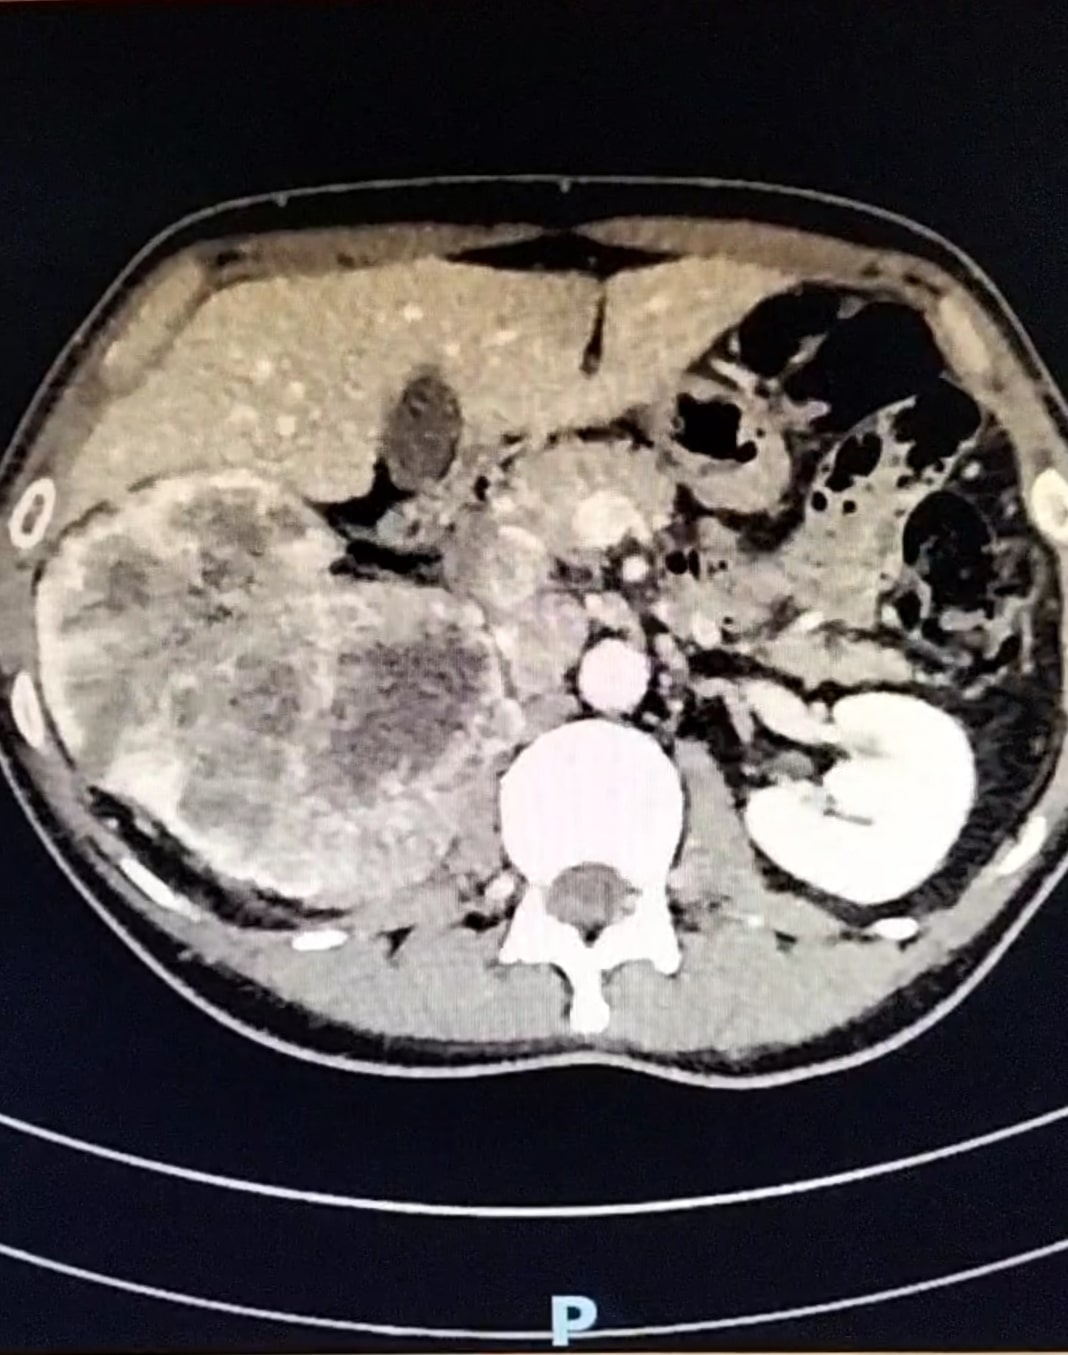

La realización de la técnica muestra riñón derecho aumentado de tamaño y una imagen compatible con una masa renal derecha con pérdida de la diferenciación cortico-medular. En contraposición se observa una silueta renal contralateral sin alteraciones.

En la analítica sanguínea se destaca deterioro de la función renal y la analítica de orina señala la presencia de hematuria. Se comenta el paciente con el Servicio de Radiología y se consensúa realización de TAC tóraco-abdominal, donde se objetiva una neoplasia renal derecha que infiltra arteria y venas principales, con trombosis de la cava desde el hilio renal hasta la porción intrahepática así como adenopatías retroperitoneales.